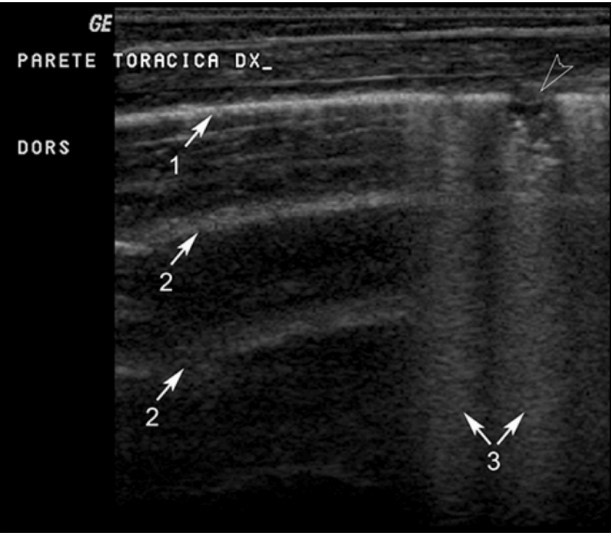

علاوه بر این، سونوگرافی قفسه سینه را می توان در معاینه ریه حیوانات بزرگ به عنوان کره اسب / اسب در نظر گرفت. هم برای حیوانات کوچک و هم بزرگ، معاینه اولتراسوند قفسه سینه در بررسی بیماری مشکوک تنفسی اندیکاسیون دارد. در حیوانات مشکوک به بیماری داخل قفسه سینه، سونوگرافی می تواند برای شناسایی پلورال افیوژن، پنوموتوراکس، بیماری پارانشیم ریوی و سایر بیماری ها استفاده شود (شکل 4).

شکل4. سونوگرافی قفسه سینه از طریق فضای بین دنده ای سمت راست در کره الاغ نر 2 ماهه ساردینیا مبتلا به پنومونی از ردوکوکوس اکوئی. رابط آکوستیک پلور یک وقفه کوتاه را نشان می دهد که ناشی از یک آبسه ریوی ساب پلورال هیپواکوی کوچک (سر پیکان خالی) است.: 1 = رابط آکوستیک پلور. 2 = A-خطوط. 3 = خطوط B.